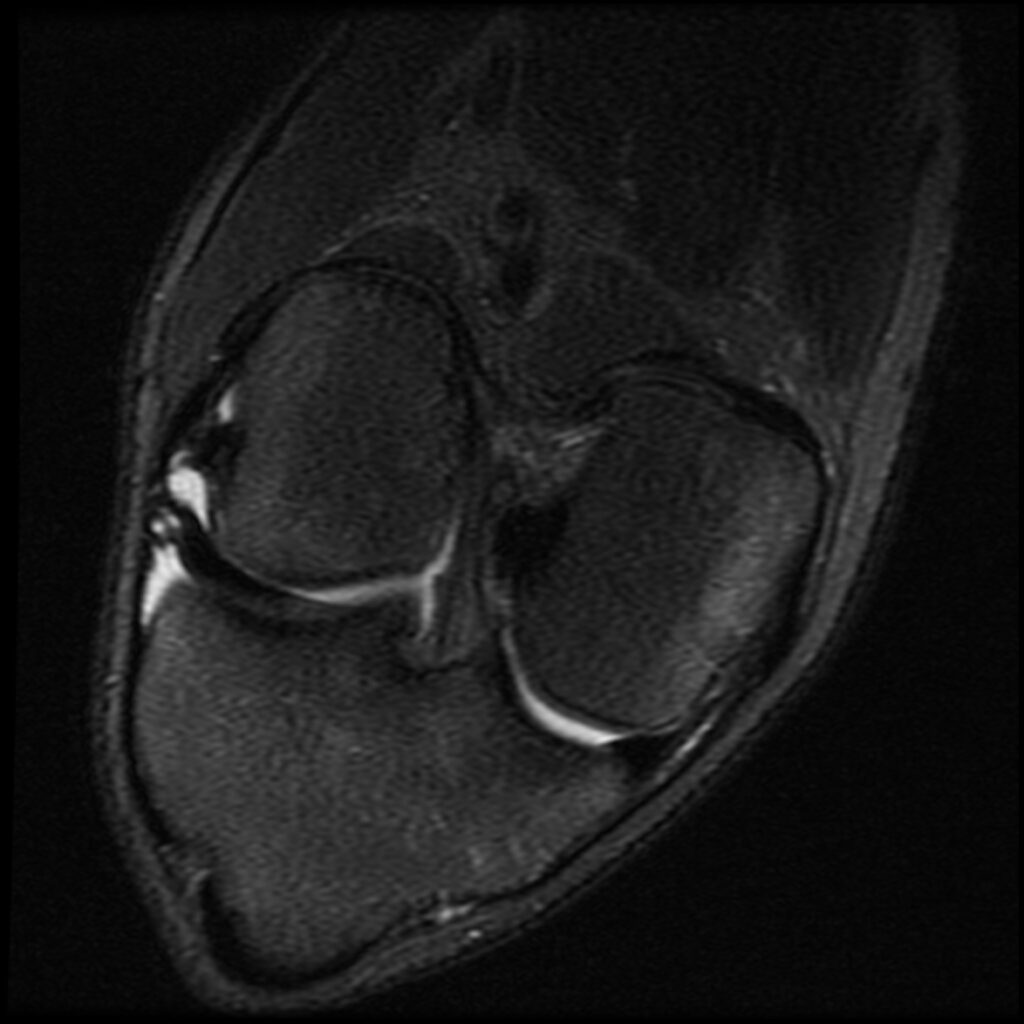

Patient D, age 19, sustained a competitive tumbling injury that involved a hard landing with the pathognomonic plant and pivot that directly tractions the ACL along its doubly obliqued path. The first MR scan was done the day after the trauma. She was initially treated 5 days post-injury. Her knee effusion was completely aspirated, then replaced with 3cc of autologous platelet-rich plasma and 5cc of platelet-poor plasma. Using ultrasound guidance, the ACL origin at the posterior femur was treated after carefully avoiding the vasculature and nerves. She was then instructed not to bear weight for 3 days, then use crutches/assisted weight bearing for 2 weeks. She was then to use a compression knee sleeve during sports or exercise. At her follow-up visit at 4 weeks, she was still having some instability at times and lateral knee pain. Her knee was evaluated with an ultrasound, and any areas of pathology seen were treated with hypertonic dextrose injection and needling technique. This included her medial and lateral collateral ligaments, and the patellar tendon and ligament. At 12-week follow-up, she continued to have some minor issues with her knee, so another evaluation and treatment were performed with hypertonic dextrose to the injured ligament and tendon areas found on the ultrasound examination. We obtained a new MR for her 16-week follow-up and noticed the ACL had re-ligamentized, and she reported full function and return to exercise. At 5-year follow-up, she claimed she was fully active, pain-free, but no longer tumbling.

Patient D Before

Patient D After